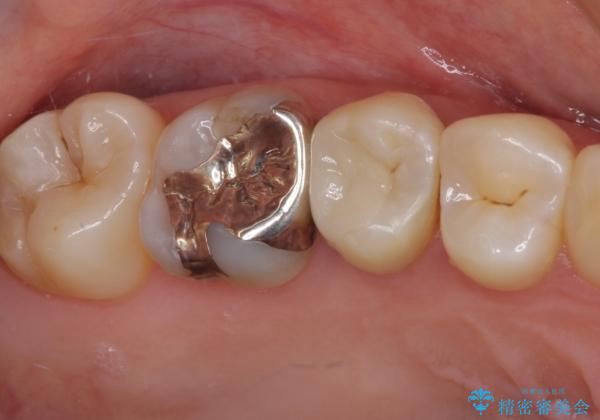

処置後に痛みを感じることはなく、冷たいものがしみることもなくなりました。

奥の大臼歯にもむし歯があったので、一緒に処置を行いました。